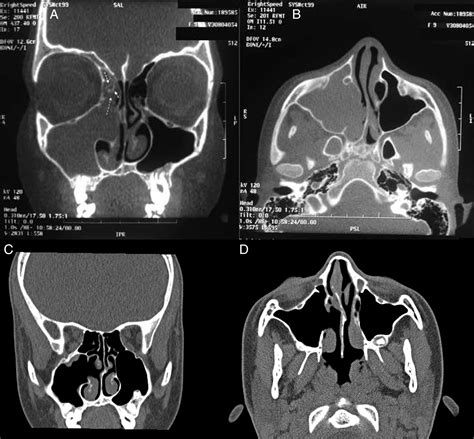

La tomografía axial computerizada (TAC) con cortes < de 1 mm permite evaluar las áreas de erosión ósea, aunque los hallazgos típicos son una masa de densidad de partes blandas con erosión ósea y microcalcificaciones en el 20% de los casos. La TAC es particularmente sensible en detectar áreas de hiperostosis, que se emplea para predecir el sitio del pedículo de implantación del papiloma invertido, aunque debe ser corroborado durante la endoscopia nasal.

Tanto la tomografía computarizada (TC) como la resonancia magnética (RM) nos permiten delimitar la extensión de la lesión antes de la cirugía, distinguiéndola del tejido inflamatorio circundante bien mediante la captación de contraste y la detección del patrón columnar que nos muestra la RM potenciada en T2 o a través de la osteolisis radiológica que se aprecia en la TC. Sin embargo, esta última no es suficiente para asegurar el diagnóstico de PI, porque puede estar presente hasta en 53% de pacientes con sinusitis crónica.